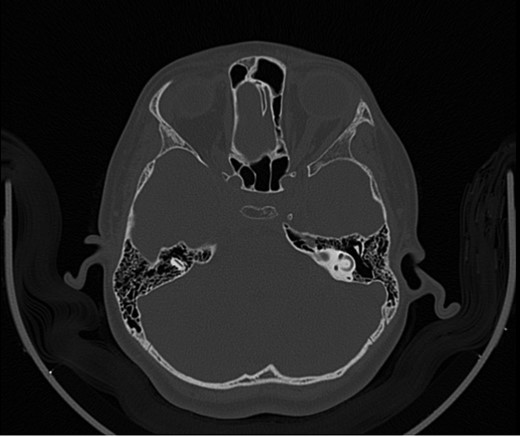

A 14-year-old male patient presented to the ENT clinic with bilateral hearing loss with no other otolaryngological symptoms. History from the patient stated a road traffic accident (RTA) 12 months ago. Meanwhile, the patient had no hearing problems prior to the RTA. Furthermore, detailed history of the accident revealed that the patient had no apparent skull injuries while pure tone audiometry (PTA) on presentation revealed bilateral conductive hearing loss and auditory brainstem response revealed right mild hearing loss and left moderate hearing loss. As a result, he was fitted with hearing aid for four months after presentation and was not compliant to it on the long-term. The patient is a non-smoker and is medically free with normal developmental milestones and negative family history of hearing complaints. Local examination of the ear revealed intact but minimally retracted tympanic membrane bilaterally. PTA was done in 2014 revealed right mild to moderate mixed hearing loss and conductive hearing loss at low frequency (Table 1). Meanwhile, the left ear had mild to moderate sensory hearing loss at high frequency (Table 2). The speech audiogram results show equal canal volume in both ears, less tympanometry pressure on the right ear and less compliance on the right ear (Table 3). The CT showed that both ossicular chains are deranged, and bilateral abnormal ossicles with no fracture or mass (Figures 1–3).

Figure 1:

CT mastoid, deranged right side ossicular disruption.